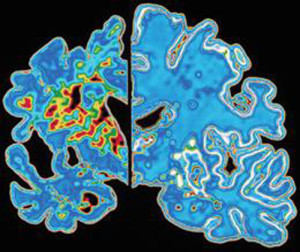

Basta un'ora di esercizio fisico alla settimana per dimezzare il rischio di sviluppare il morbo d'Alzheimer. Lo ha scoperto un...